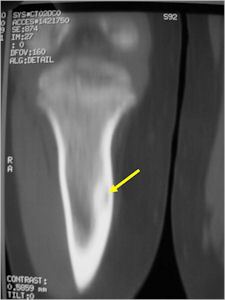

CT Scan:

- Well defined nidus with a smooth peripheral margin; +/- mineralization (CT more sensitive than XR and MRI for detecting mineralization); CT is better for detecting nidus in presence of exuberant sclerosis